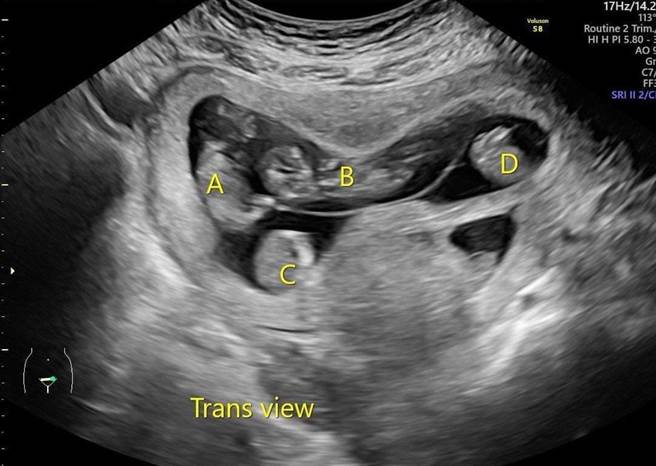

直到郭小姐上搜寻台北长庚医院妇产部教授级主治医师、台湾母胎医学会理事长萧胜文的射频烧灼减胎技术,一切才有了转机。萧胜文检查、评估后,同意接手郭小姐这位高危险妊娠产妇。郭小姐透露,拿到孕妇手册的一霎那,既兴奋又感动,认为终于有她和宝宝归属的地方,便稳定在台北长庚产检追踪。由于4胞胎早产与母体併发症的风险太高,郭小姐决定减胎,在第15周接受射频减胎手术后,怀有同卵3胞胎。

萧胜文指出,郭小姐试管一开始植入2个胚胎,其中1个胚胎发育为罕见的同卵4胞胎,发生率约6000万分之一,另1个胚胎自行萎缩。她与家人寻求协助时几乎都是建议直接放弃4个孩子,转诊到台北长庚时,已怀孕11周。由于4胞胎发生早产与母体併发症的风险太高,因此建议减胎,经超音波精准定位,找出位子适合的胎儿,再以射频烧灼(RFA)阻断胎儿的血流供给,达成减胎的目的,这也是目前的国际趋势。